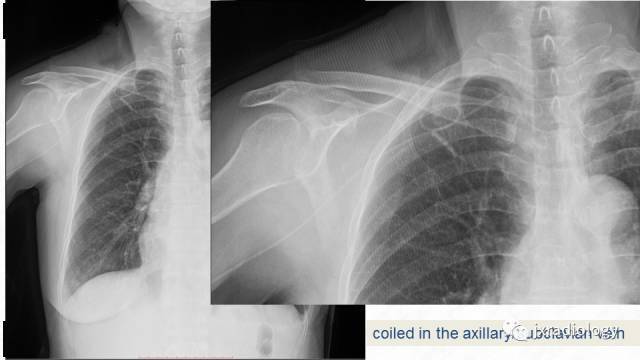

picc尖端的胸片定位

图片尺寸640x360